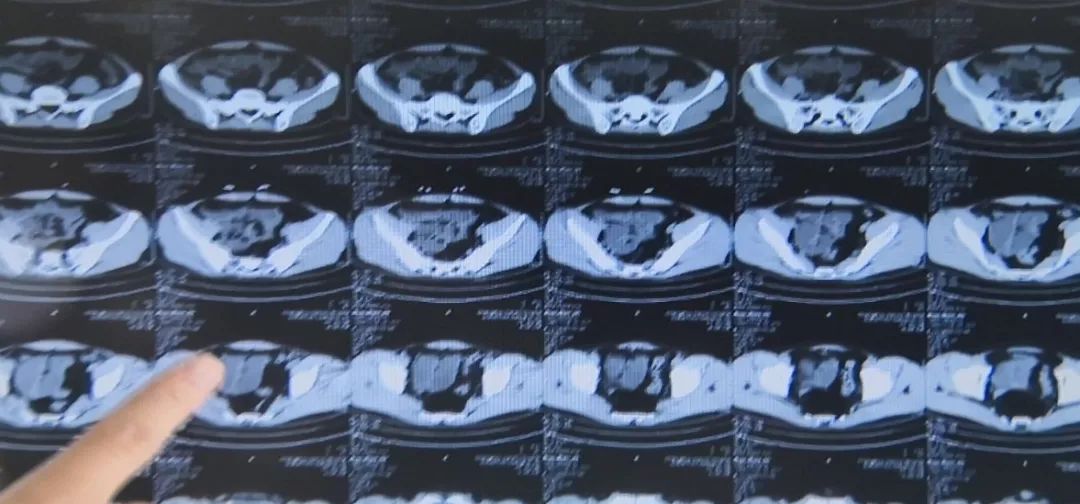

一阵阵的绞痛让刘先生更难受,于是就到医院就诊,才知道因为自己自服止泻药,反而导致了“急性不完全性肠梗阻”。